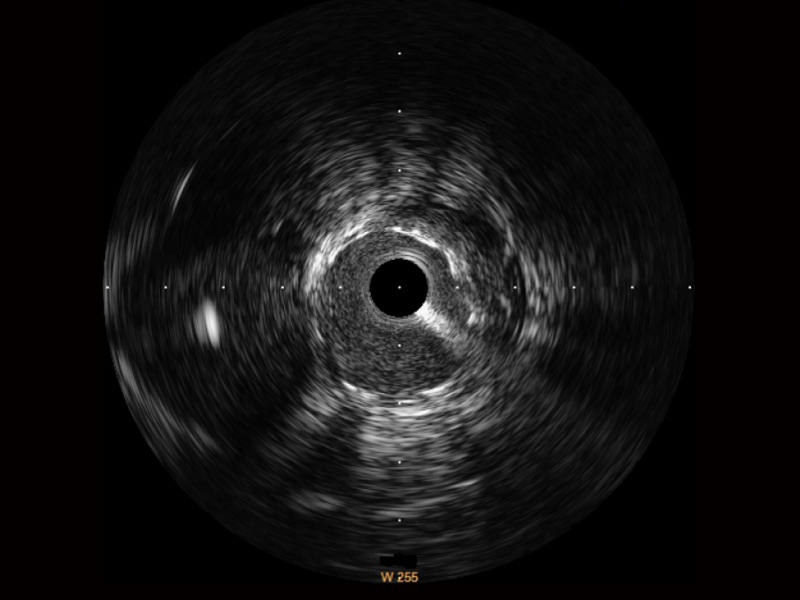

• 云顶集团官网宽频IVUS图像

• 传统IVUS图像

对比传统IVUS导管成像,云顶集团官网宽频IVUS图像的近场支架梁显影更细腻,远场中膜外血管仍清晰可辨,兼顾远中近,兼顾分辨力与穿透深度